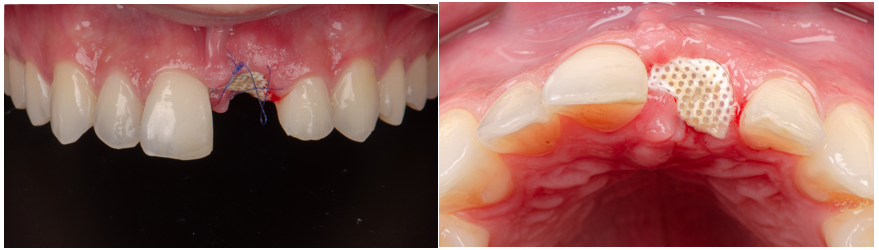

Com o objetivo de preservar o volume ósseo e a morfologia gengival, foi realizada uma regeneração óssea guiada (ROG) com o Extra Graft XG-13 aplicado na região vestibular para preenchimento do GAP entre o implante e a parede óssea. Na sequência, foi colocada uma membrana Cytoplast, em PTFE de alta densidade, adaptada sob o tecido gengival e estabilizada por sutura com nylon azul, promovendo selamento do sítio cirúrgico.

Essa associação de biomateriais — enxerto particulado e membrana não reabsorvível — ofereceu as condições ideais para proteger o implante, preservar o volume tecidual e guiar o processo de regeneração com previsibilidade.

Após dez dias, foi realizada a remoção das suturas, observando-se bom aspecto clínico e ausência de sinais de inflamação. Já no 21º dia, com a cessação da competição tecidual, foi feita a remoção da membrana Cytoplast, de forma simples e segura e sem a necessidade de nova intervenção cirúrgica.